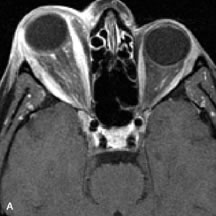

Lymphomas have MRI characteristics similar to those of inflammatory lesions in that they are hypointense to fat and isointense to muscle on T1-weighted images (Fig. 22). They may appear hyperintense to fat on T2-weighted images, perhaps owing to less fibrosis than that seen in orbital inflammatory pseudotumor, although this is not a consistent finding.31,50,66 Lymphoid tumors typically enhance moderately after contrast injection. Unfortunately, studies have shown that tumor density and homogeneity are similar between inflammatory and malignant orbital infiltrates, and MRI cannot differentiate these lesions.72,73

Fig. 22. A and B. T1- and (C) T2-weighted MR scans demonstrate a poorly defined multicompartmental mass enveloping the lateral rectus, superior rectus, and levator palpebrac superioris muscles. The lesion is isointense to brain on T1- and T2-weighted scans, as is typical for highly cellular neoplasms. D. Postcontrast fat-suppressed T1-weighted scan demonstrates intense enhancement of the infiltrating intraconal and extraconal tumor.